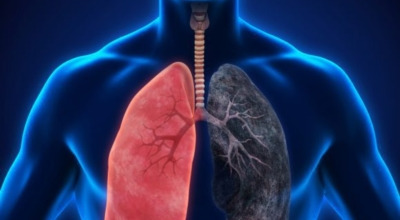

폐암의 원인 ① 흡연

폐암의 주요 발병 원인은 흡연입니다. 담배에는 많은 유해 물질과 암을 유발하는 성분들이 포함되어 있는데, 흡연자는 비흡연자에 비해 폐암 위험이 15배에서 80배까지 높아집니다. 특히 흡연량이 많거나, 어린 나이에 흡연을 시작했거나, 흡연 기간이 길수록 위험도는 더욱 커지게 됩니다.